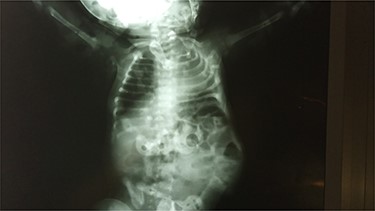

After studying the case, we decided to perform primary repair of the abdominal wall defect without meshplasty since the diameter of the aperture was <5 cm. An oblique left lumbar incision was performed above the hernia, revealing a defect measuring 4 cm in diameter in the upper lumbar triangle. Dissection of the peritoneum and hernial sac was performed starting from the margins of abdominal muscles (Fig. 4), the hernial sac was internally reduced and the muscular margins were closed by simple continuous sutures made from prolene 0 (Fig. 5). Complete closure of the defect was confirmed and a draining tube was inserted subcutaneously before closing the skin. The drain was removed after 2 days; the stitches were removed after 10 days. The patient was faring well after the surgery. Recurrence of the hernia was not reported. We recommended that the patient should be followed up by an orthopedist for the correction of disability, which is caused by LCVS.

The consolidation stage after reduction of the hernia sac of the abdominal cavity.